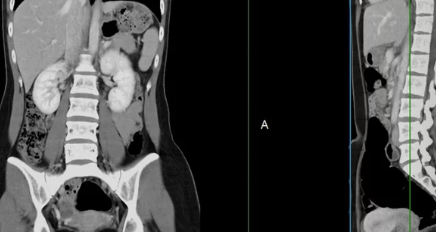

✔ 2. 영상 검사 (CT & MRI)

→ 부신 종양의 크기 및 전이 여부 확인